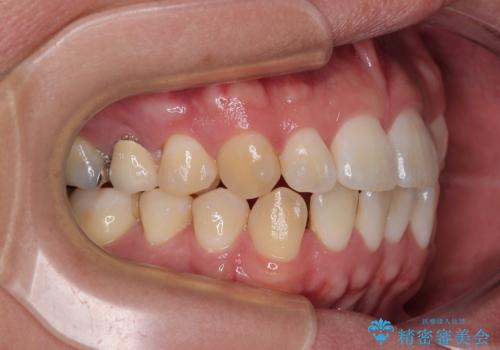

前歯のデコボコをささっと治す 短期間でのインビザライン矯正治療

- 前歯の反対咬合などを気にして来院された患者様です。

ワイヤー矯正、マウスピース矯正どちらでも対応可能であったので、ご本人の希望によりインビザラインにて矯正治療を行うこととしました。

毎日の装着時間をしっかりと守ってくださり、1年強の短期間で、あっという間に治療を終えることができました。